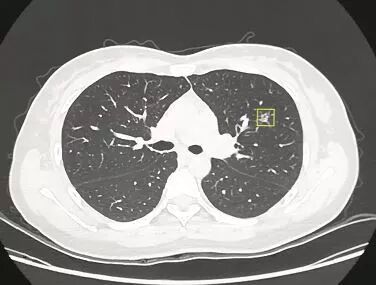

随着人们保健意识的增强,螺旋CT的普及, 越来越多的肺小结节得以早期发现。 对于病灶越小,尤其是位于肺深部的结节,肺部的多发结节, 常常难以定位并常需行肺段切除。 人体的左肺借斜形裂分成上、下两叶;右肺借横形裂和斜形裂分成上、中和下叶三叶。而左、右肺各有十个肺段, 由肺段支气管及其所属的肺组织组成。 肺段切除手术除了解剖操作困难,另一难点是不易准确标记出段与段的交界面,目前常规的白光胸腔镜使用膨胀萎陷法,需要等待20分钟, 就是由于上述问题的存在,导致手术时间的延长和手术难度的明显增加。 两种方法的区别详见下表: 为解决上述问题,最大限度使手术微创化, 2014年11月起在省内率先开展单孔胸腔镜手术的南京胸科医院杨如松团队, 又在最近引进了加拿大PINPOINT荧光胸腔镜,为肺段切除再添利器。 据杨如松院长介绍,荧光胸腔镜运用最新颖的技术:将荧光造影剂吲哚菁绿通过静脉或局部注射,与血红蛋白或白蛋白结合后,释放荧光,从而在手术中显像。 荧光胸腔镜与普通白光电视辅助胸腔镜不同的是: 术中对定位肺小结节区域进行荧光显影以及肺段平面的定位,病灶或肺段立刻“显露真身”,从而达到精确切除肺结节或肺段的目的,并最大程度地保留患者肺功能。 目标肺段“精准切除”此外,荧光造影剂吲哚菁绿没有放射性,不参与体内化学反应,无辐射,无毒副作用,且排泄快,病人非常安全。同时术中实时评估, 手术操作、观察同步进行,进而缩短了手术时间。 据杨院长介绍,运用加拿大PINPOINT荧光胸腔镜技术可以 最大限度减少正常肺组织的损伤,进而最大限度保留肺功能,结合我院在省内最新开展、业已多年、技术纯熟的单孔胸腔镜技术和非插管全身麻醉技术; 我科的肺段手术可以使患者创伤更小,恢复更快,从而让患者在极致微创的理念下,健康更多受益。